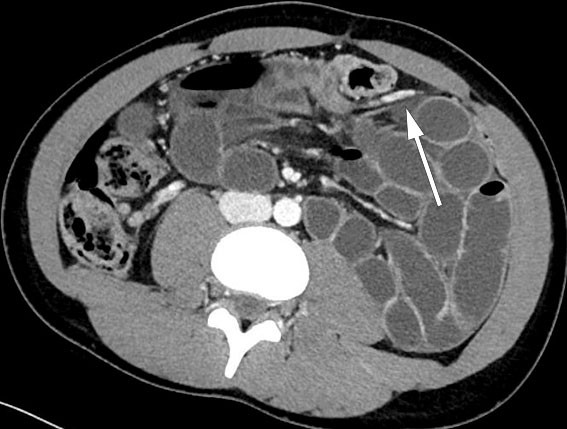

Ved regranskning av pasientens CT-bilder forløp v. mesenterica inferior ventralt for de hernierte tynntarmsslyngene. Dette ble også sett peroperativt og samsvarte med diagnosen paraduodenalt brokk (figur 2)